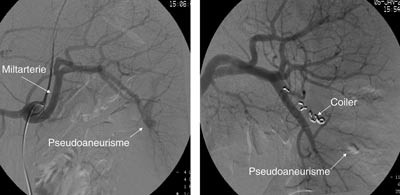

Pasient 1. En 16 år gammel gutt ble henvist til lokalsykehuset med spørsmål om miltskade. Han hadde seks dager tidligere falt under fotballtrening. Pasienten kom gående og klagde over magesmerter. CT-undersøkelse supplert med arteriell kontrastfase gav tydelig fremstilling av en rund, velavgrenset og høyattenuerende lesjon (fig 2a). På bildene fra vanlig venøs kontrastfase var denne strukturen dårligere fremstilt (fig 2b). Pseudoaneurisme ble mistenkt. Skaden ble vurdert som grad IV. Pasienten ble overflyttet til Ullevål universitetssykehus hvor det ble utført angiografi som bekreftet diagnosen. Deretter foretok man embolisering (fig 3). Prosedyren var vellykket og pasienten ble utskrevet etter én uke.

Pasient 2. En 20 år gammel mann ble utsatt for en trafikkulykke. Han var komatøs og ble intubert på skadestedet. CT-undersøkelse ved Ullevål universitetssykehus viste venstresidig pneumothorax og costafrakturer. I milten forelå en laserasjon kaudalt (skadegrad III), men normale funn i hilusnivå (e-fig 4). Pasienten ble observert og overflyttet til lokalsykehus etter tre dager. Seks dager etter traumet ble det gjort en CT-kontroll med arteriell kontrastfase. Denne viste en tilkommet, høytattenuerende lesjon ved milthilus, forenlig med et pseudoaneurisme (e-fig 5). Pasienten ble flyttet tilbake til Ullevål universitetssykehus hvor det ble utført angiografi med embolisering (e-fig 6). Ultralydkontroll samme dag viste opphørt sirkulasjon i lesjonen. Tre dager senere ble pasienten utskrevet.